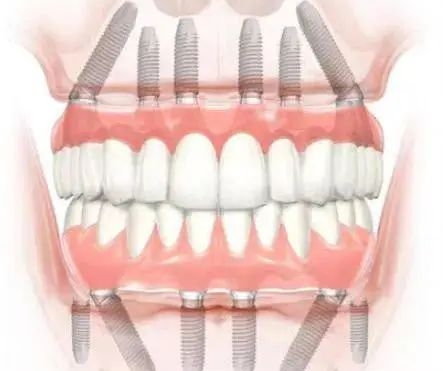

• ALL-ON-4/6即刻負(fù)重技術(shù):僅需4–6顆植體即可支撐整排牙齒,當(dāng)天種牙當(dāng)天吃飯